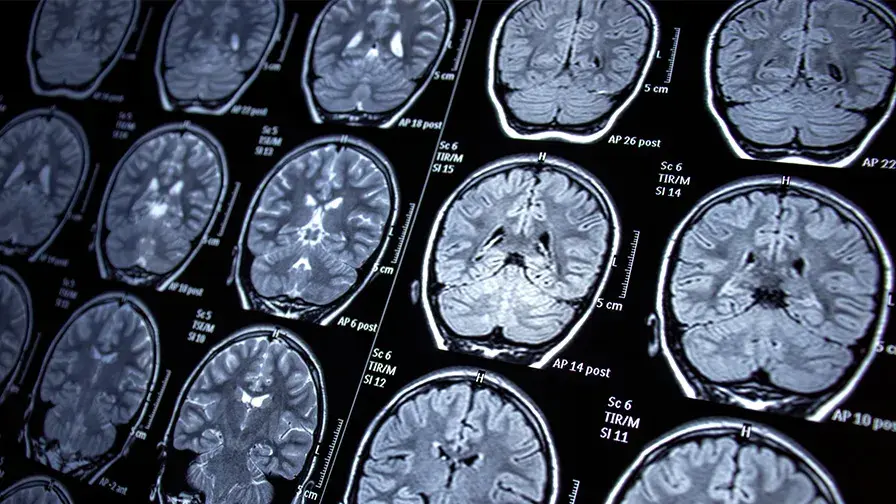

Les résultats des chercheurs ont fait l’objet d’une publication dans The Lancet Neurology. Le professeur Fanny Mochel du service de génétique médicale de l’hôpital Pitié-Salpêtrière AP-HP et de Sorbonne Université et de l’Institut du Cerveau, en collaboration avec des équipes de recherche clinique réparties dans huit pays et la biotech espagnole Minoryx Therapeutics, a mis en évidence les effets protecteurs de la leriglitazone dans l’évolution de l’adrénoleucodystrophie, une maladie génétique rare dans laquelle on observe une atteinte de la substance blanche du système nerveux central.

• La plupart des maladies neurodégénératives rares souffrent de l’absence de traitements efficaces. C’est le cas de l’adrénoleucodystrophie liée à l’X (ou X-ALD), une affection héréditaire qui touche six à huit naissances sur 100 000. Elle se caractérise par l’accumulation excessive d’acides gras à très longues chaînes dans les tissus du corps, notamment au niveau du cerveau, de la moelle épinière et des glandes surrénales.

Quand ils atteignent l’âge adulte, ces patients présentent une dégénérescence de la moelle épinière. En conséquence, ils manifestent souvent une adrénomyéloneuropathie (AMN) à l’origine de symptômes chroniques handicapants, en particulier une raideur à la marche et des troubles de l’équilibre qui augmentent le risque de chutes. Des troubles urinaires sont fréquemment associés.